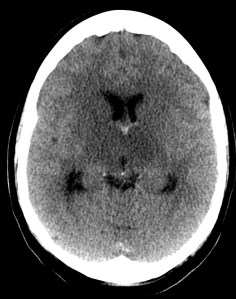

Se decide ingreso de la paciente para estudio y, ante el incremento de la cefalea y empeoramiento del estado general, se realiza nuevo TC de cráneo sin contraste. Veámos las imágenes.

1- TAC SIN CONTRASTE:

Se realiza para descartar otros procesos como infartos, tumores o infecciones.

- Signos directos: Cuerda Hiperdensa. En caso de trombo en las venas corticales, se observa el signo de la cuerda hiperdensa intraluminal. El trombo puede permancer hiperdenso 2 semanas para luego hacerse isodenso. La S y E de este signo son bajas.

- Signos indirectos: Cambios en el parénquima debido a la isquemia por perturbación del flujo venoso, produciéndose edema, infartos o hemorragias. Los infartos no hemorrágicos son las lesiones más frecuentes, suelen ser de localización subcortical, no sigue una distribución arterial y se localiza en las inmediaciones del seno afectado. Una afectación del SSS (el más frecuente) produce afectación bilateral en los territorios frontales, parietales y occipitales. Una afectación del ST afecta los lóbulos temporales. El seno recto afectado produce lesión profunda, en el tálamo. Los infartos hemorrágicos son menos frecuentes, se han descrito sangrados subdurales, subaracnoideos e incluso abiertos a ventrículos. El edema que se produce puede originar efecto masa con desplazamiento de la línea media e incluso disminución de ventrículos (dificil de valorar en jóvenes). La hidrocefalia marcada no se suele producir.